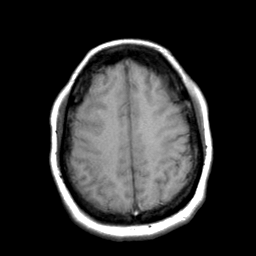

Cerebral hemorrhage, MR Study mr-t1 -- Slice #18

[Home][Help][Clinical] Slice 18